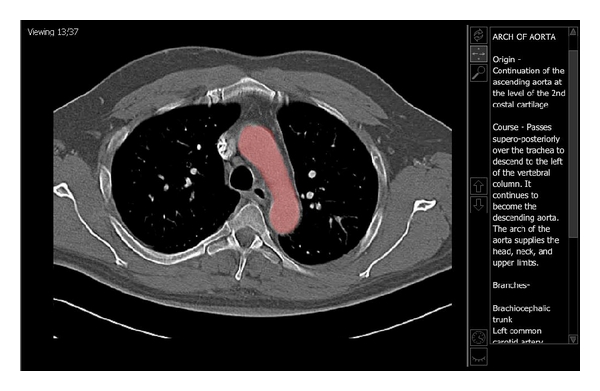

Current generations of graduate students have been immersed in technology from their early school years and have high expectations regarding digital resources. To better meet the expectations of Gross Anatomy students at our institution, electronic radiology teaching files for first-year coursework were organized into a web site. The web site was custom designed to provide material that directly correlated to the Gross Anatomy dissection and lectures. Quick links provided sets of images grouped by anatomic location. Additionally, Lab and Study Companions provided specific material for the students to review prior to and after lectures and gross dissections. Student opinions of this education resource were compared to student opinions of the prior year's digital teaching files. The new content was ranked as more user friendly (3.1 points versus 2.3 points) and more useful for learning anatomy (3.3 points versus 2.6 points). Many students reported that using the web portal was critical in helping them to better understand relationships of anatomical structures. These findings suggest that a well-organized web portal can provide a user-friendly, valuable educational resource for medical students who are studying Gross Anatomy.